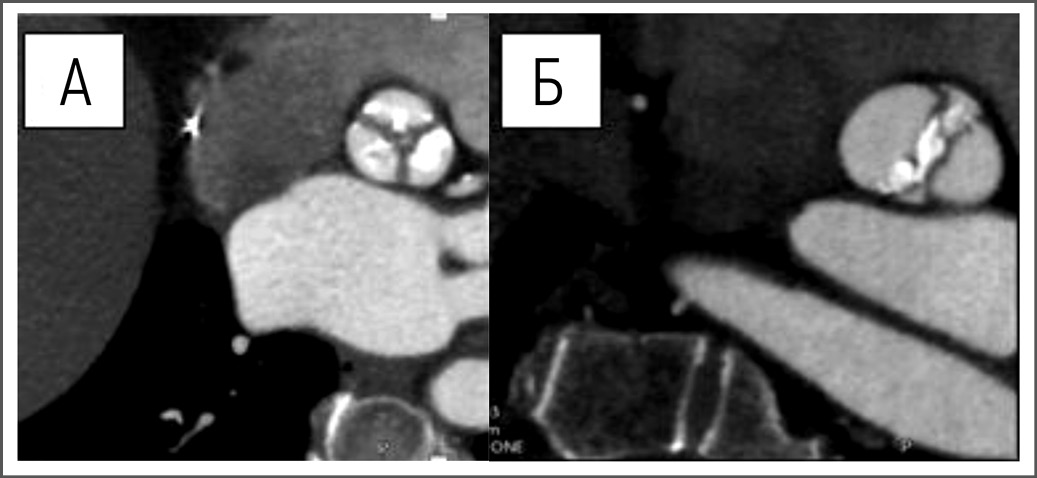

Временные систолические интервалы АТ и отношение AТ/ЕT были получены в 5-камерной апикальной проекции непрерывно- волновым допплером. ЕТ измеряли как время от начала и до конца систолического кровотока, AT – как временной интервал от начала систолического кровотока до максимальной его скорости; после рассчитывали отношение AT/ET (рис. 1).

Рис. 1. Систолические временные интервалы АТ и AТ/ЕT. / Fig. 1. Systolic time intervals AT and AT/ET.